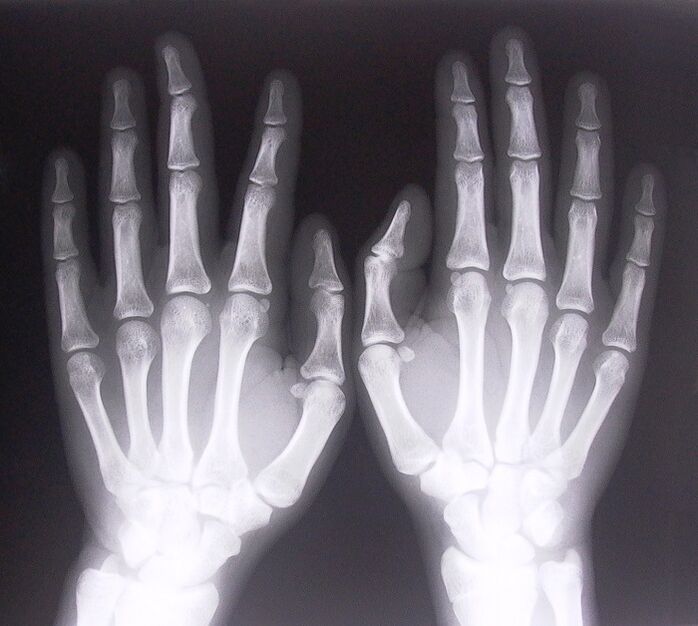

- Stenotic conjunctivitis.To identify the cause of the disease, it is necessary to undergo an X-ray.The symptoms are characteristic: painful movement of the hand, loop of the clenched palm.Also, when expanding, clicks are usually heard.

- Get x-rays.